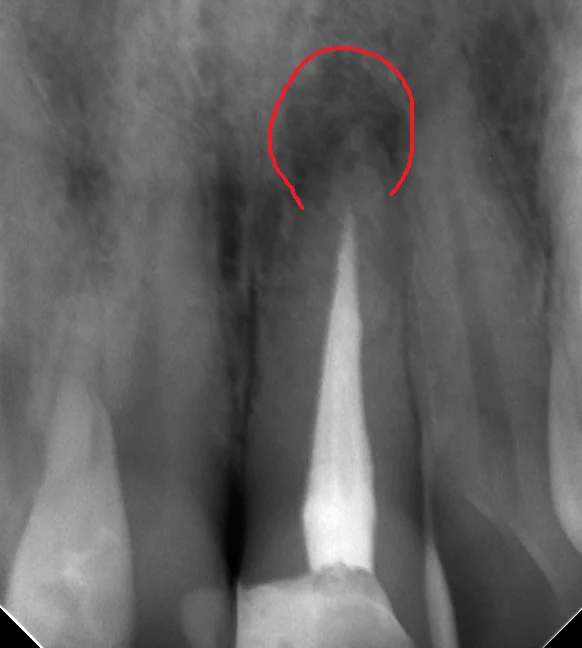

根管内が綺麗に出来たので、根管充填(最終的なお薬を詰めること)を行ったときのレントゲンがこちらです。

根の先の膿に変化はありません。

治療開始から根管充填まで治療回数は3回、治療期間は1ヵ月半くらいでした。

この膿はうちのレントゲンで確認出来るだけでも、前の院長の時代からありましたので、最低でも4~5年以上前から放置されている状態でした。

当然それだけの年月をかけてゆっくりと骨が溶かされて行っていますので、1ヵ月半程度で直ぐに骨が出来てくるという事はありません。